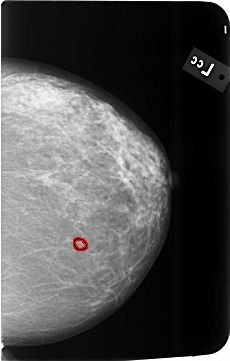

B_3493_1.LEFT_MLO

LEFT_MLO LINES 5800 PIXELS_PER_LINE 3712 BITS_PER_PIXEL 12 RESOLUTION 50 OVERLAY

FILE: B_3493_1.LEFT_MLO.OVERLAY

TOTAL_ABNORMALITIES 1

ABNORMALITY 1

LESION_TYPE CALCIFICATION TYPE PLEOMORPHIC DISTRIBUTION CLUSTERED

ASSESSMENT 4

SUBTLETY 3

PATHOLOGY BENIGN

TOTAL_OUTLINES 1

BOUNDARY